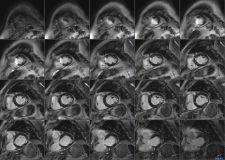

In the area of cardiology, Philips will announce the commercial release of the 32-channel cardiac coil for both Achieva 3.0T and 1.5T systems.